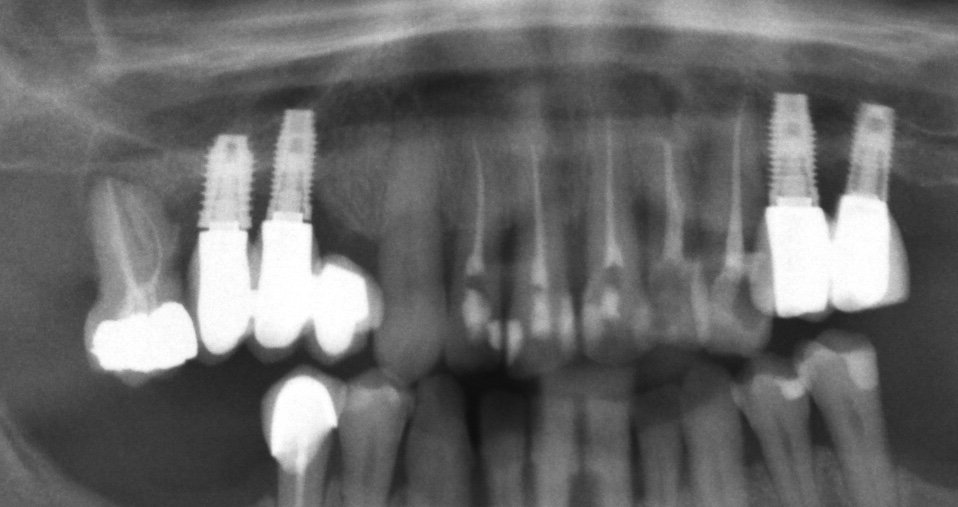

No tenemos información del modelo de implantes sup-inf

Acude paciente a nuestra clínica para ver si la podemos ayudar. No se sujetan bien las prótesis que lleva. La Clinica dónde le colocaron los implantes ha desaparecido. Necesitamos saber [...]